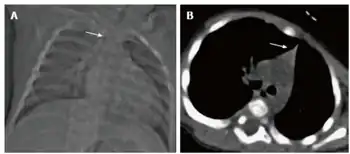

| Thymic hypoplasia in infant with primary immunodeficiency- a) Small thymus b) triangular configuration of thymus | |